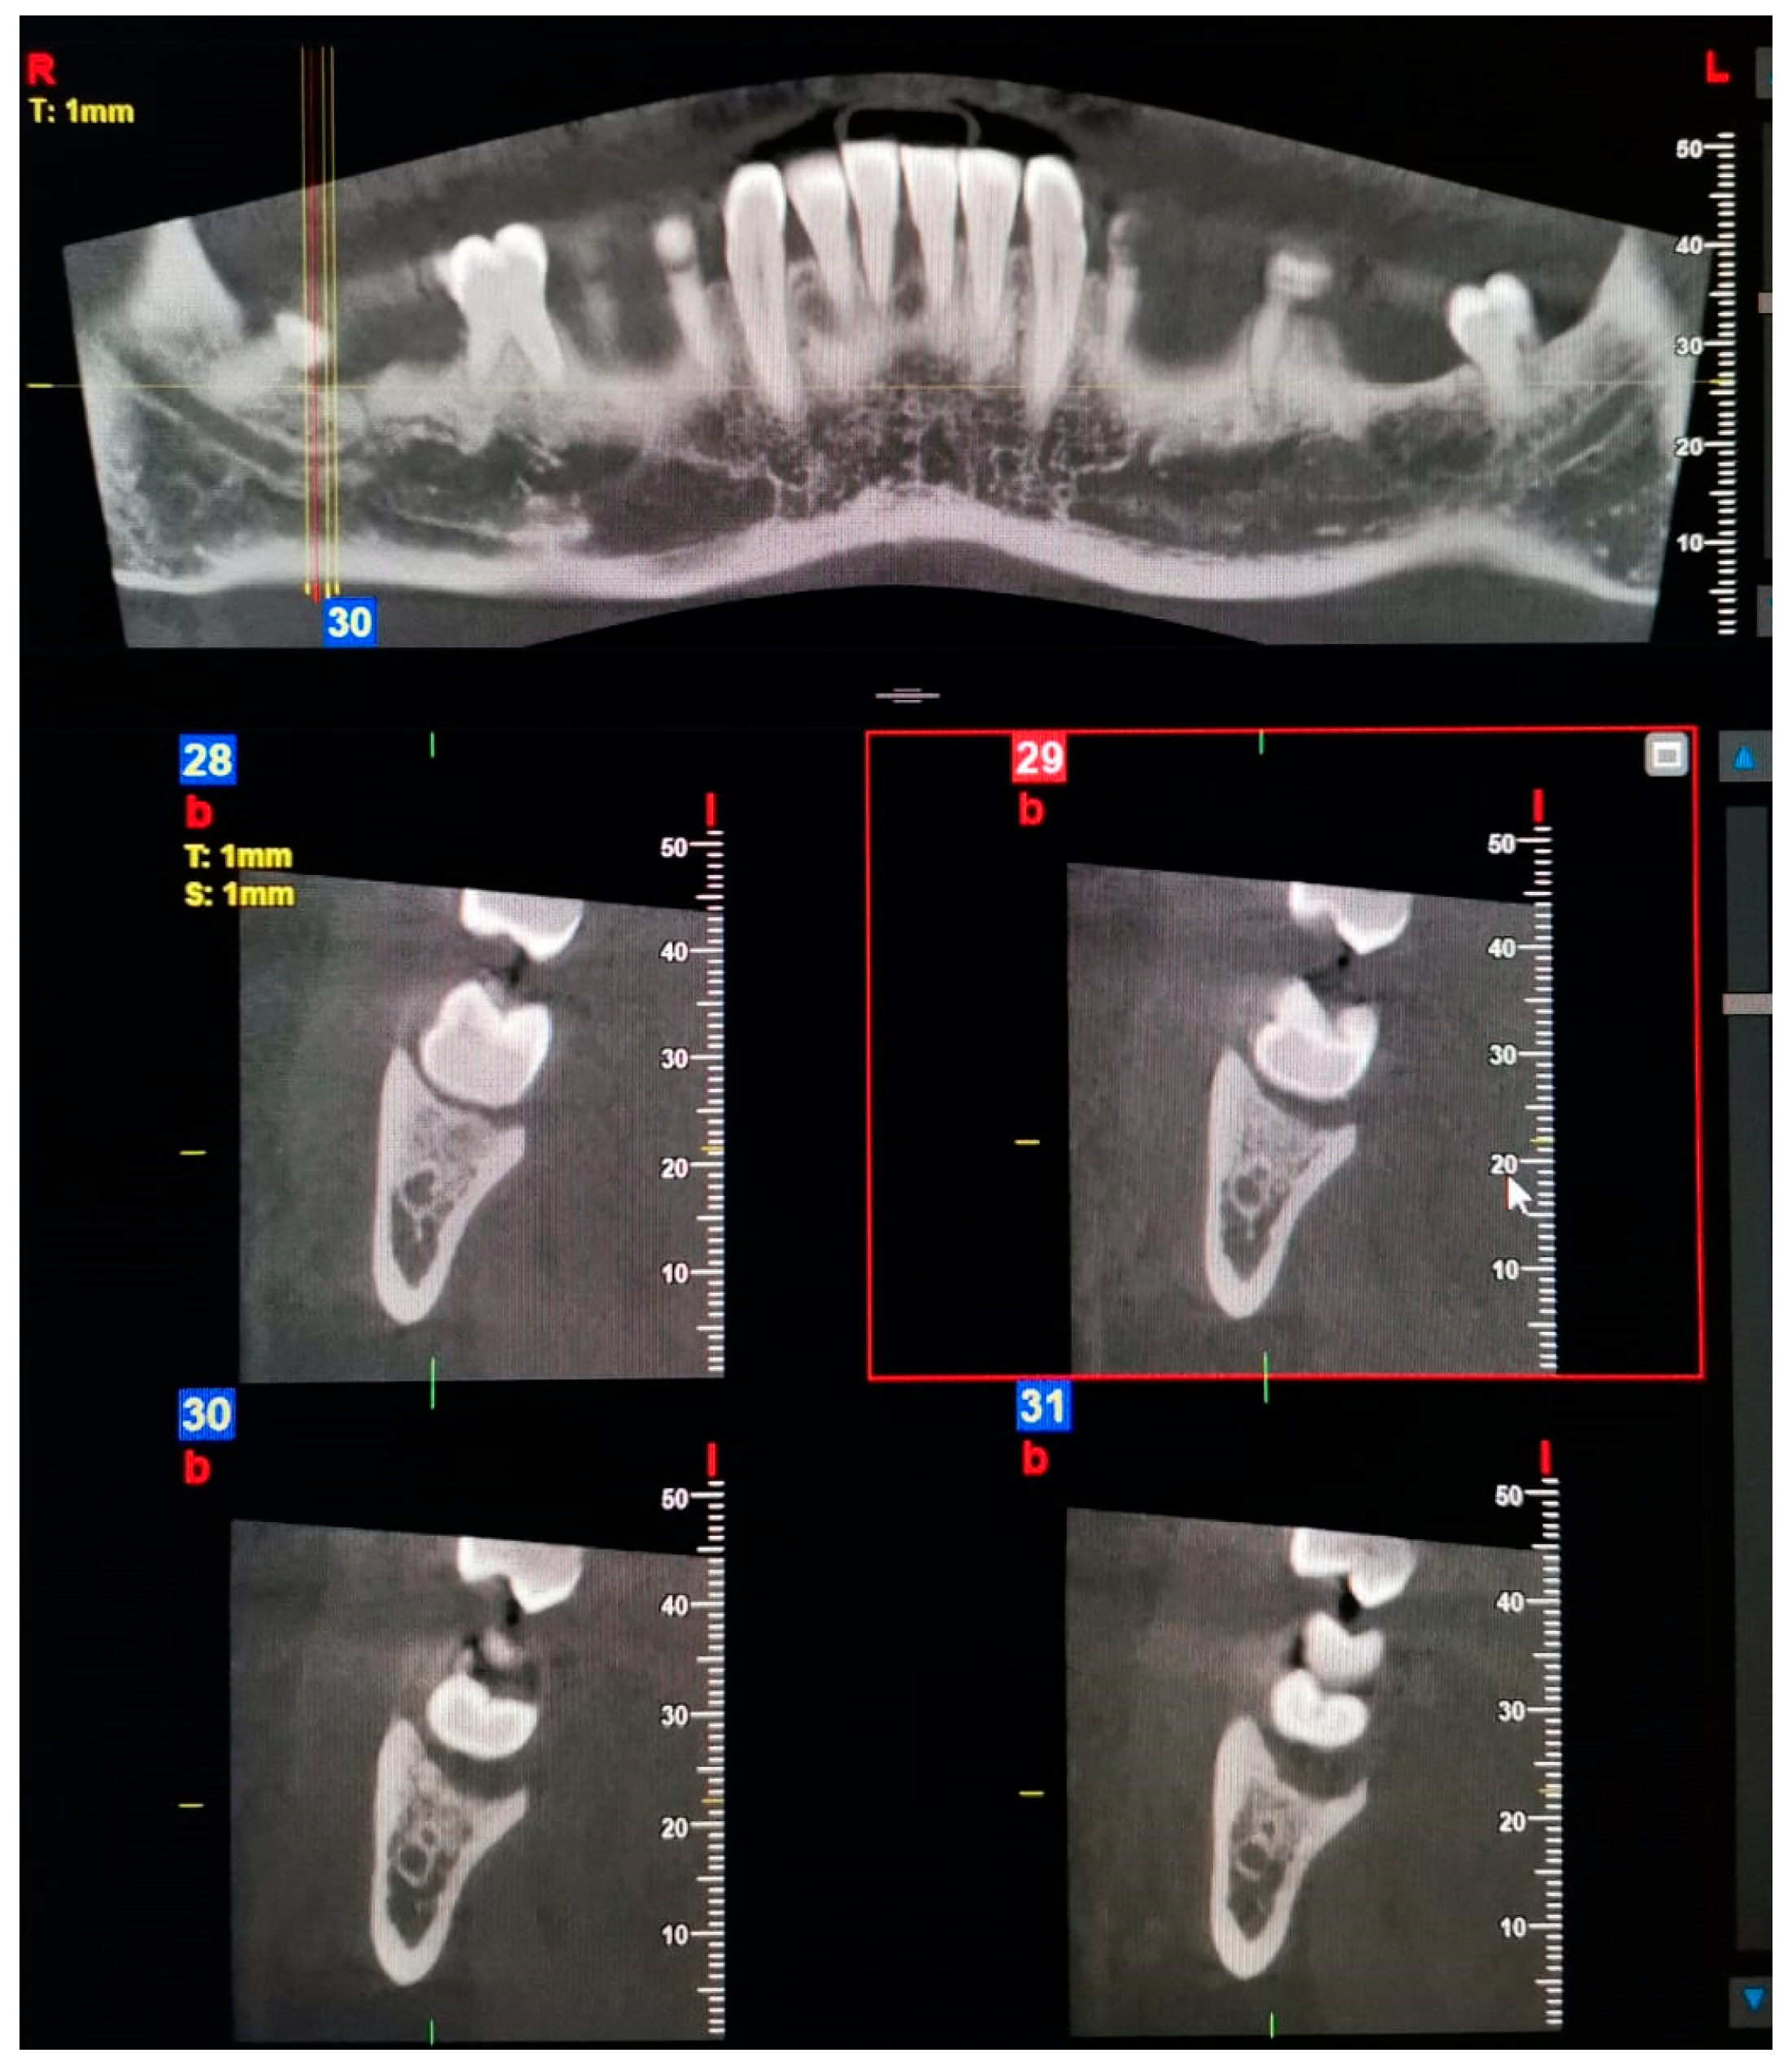

| 2—Dental | The dental canal, which bifurcates from the mandibular canal in the mandibular ramus region, courses forward, reaching the roots of the molars. |